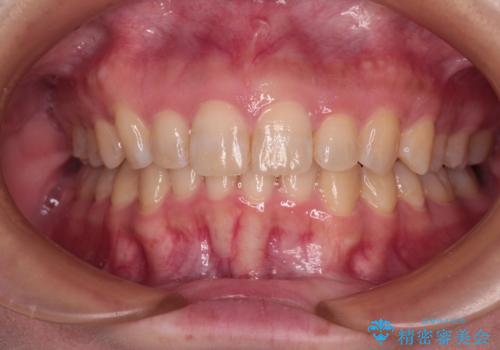

- 前歯の突出感を気にして来院された患者様です。

左右ともに奥歯の咬み合わせが上顎前突となっており、上顎前歯が飛び出している状態でした。

奥歯の咬み合わせはしっかりと改善され、前歯の突出感も改善されました。